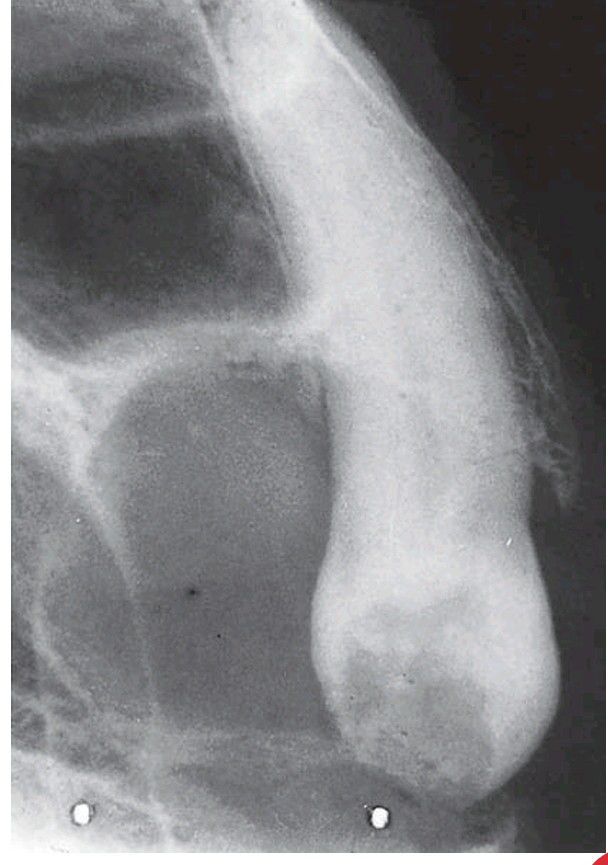

Resorption of tooth associated with a dentigerous cyst.

The crown of this buried canine within the cyst shows resorption. This is unusual and is seen only in long-neglected cysts, as in this otherwise edentulous patien